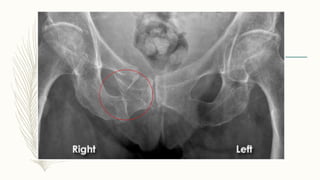

– Las fracturas de pelvis son o no estables, dependiendo de que

interrumpan el anillo pélvico en uno o más puntos.

Grupo A-2

– Sin compromiso del anillo pelviano posterior

– A-2-1: fractura de cresta iliaca

– A-2-2: ramas ilio-isquiopubiana unilateral

– A-2-3: ramas ilio-isquiopubiana bilateral

Fracturas tipo B

– Son fracturas en las que existe una interrupción parcial del anillo

pelviano posterior y por lo tanto parcialmente inestables, siendo su

característica la inestabilidad rotacional.

Grupo B-1

– Fracturas por rotación externa o «en libro abierto»

– B-1-1: la lesión parcial posterior puede estar localizada en la articulación

sacroiliaca anterior

– B-1-2: lesión localizada en el sacro

Grupo B-2

– Fracturas por compresión lateral o rotación interna:

– B-2-1: fractura por impactación anterior del sacro

– B-2-2: luxofractura parcial sacroiliaca

– B-2-3: fractura incompleta posterior del hueso iliaco